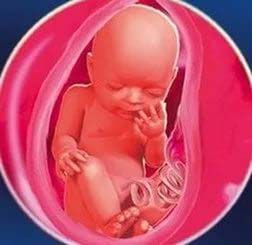

29 неделя беременности: сколько это месяцев и чего ожидать?